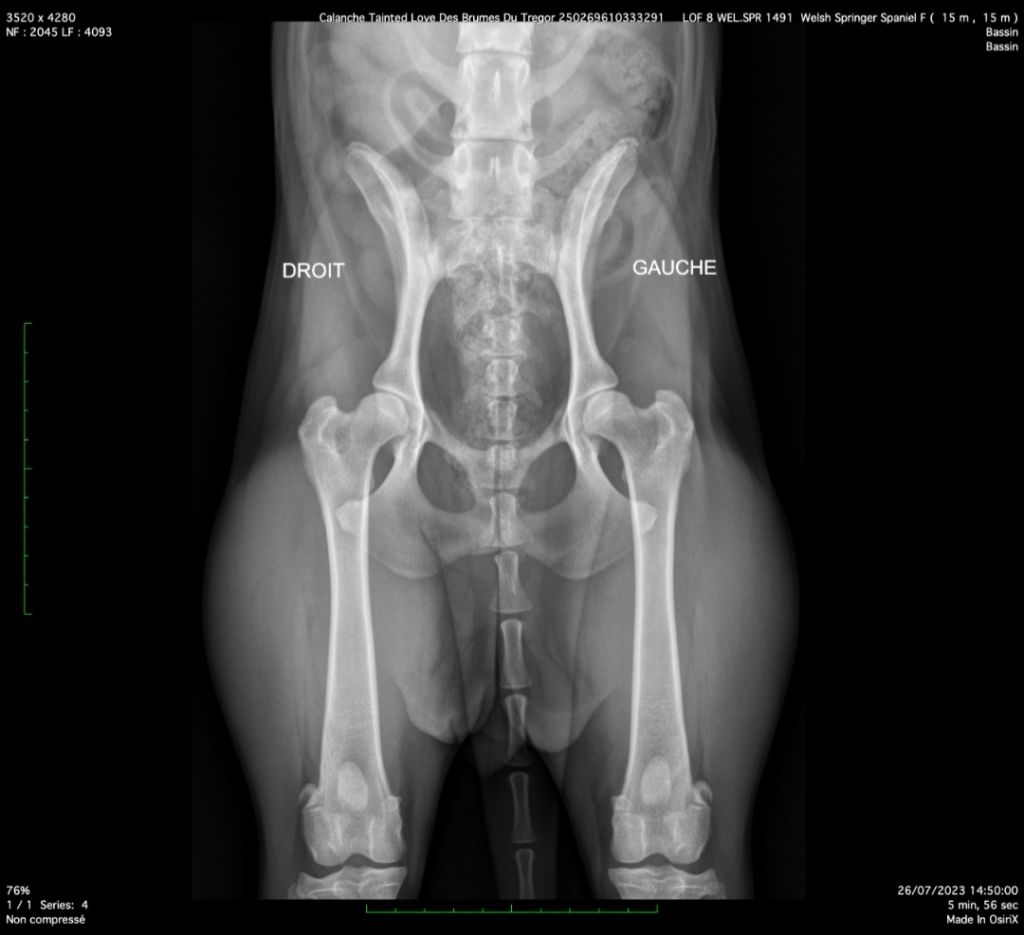

Atrophie rétinienne progressive : PRA - 0 = indemne Dysplasie Hanche : HD - C = légère dysplasie (cf.cliché radio ...!!!) |